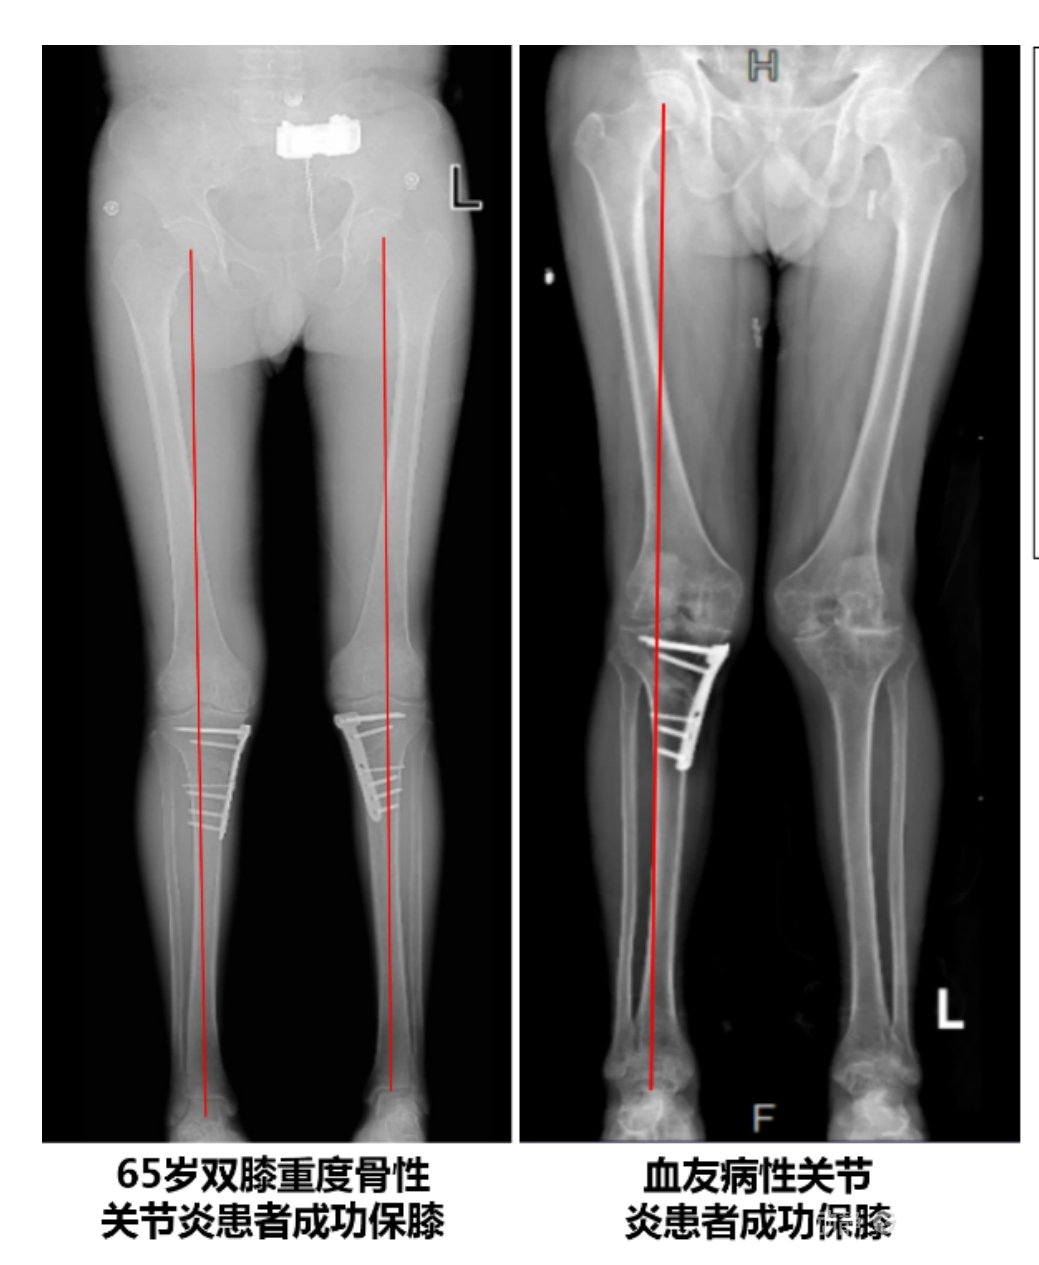

4.2 APTT-HTO脛骨高位截骨術(shù)

2025年7月,貴州醫(yī)科大學(xué)附屬醫(yī)院骨科團(tuán)隊(duì)原創(chuàng)研發(fā)的腘肌前結(jié)節(jié)中脛骨高位截骨保膝術(shù)(Anterior Popliteus Transtibial Tuberosity-High Tibial Osteotomy, APTT-HTO)及其提出的脛骨結(jié)節(jié)分區(qū)與腘肌保護(hù)理論,登上了國(guó)際頂尖學(xué)術(shù)舞臺(tái)。該成果在全球最具影響力的專業(yè)會(huì)議之一——日本骨科協(xié)會(huì)第98屆年會(huì)上進(jìn)行了兩次學(xué)術(shù)發(fā)言。[8]

該手術(shù)具有經(jīng)皮微創(chuàng)、保留原生膝關(guān)節(jié)結(jié)構(gòu)、符合階梯治療原則等優(yōu)勢(shì),通過調(diào)整下肢力線可促進(jìn)部分軟骨再生,術(shù)后關(guān)節(jié)功能接近正常(如下蹲、爬山),患者還能從事中重體力勞動(dòng)。相比其他術(shù)式,其有效規(guī)避了髕骨低位、血管損傷、合頁(yè)骨折等潛在并發(fā)癥。

目前,APTT-HTO技術(shù)已成功應(yīng)用于千余名患者,幫助保留自身膝關(guān)節(jié)。此類保膝手術(shù)適用于單間室膝關(guān)節(jié)炎患者(如 “羅圈腿”),核心是通過調(diào)整力線糾正畸形,減輕磨損間室壓力、發(fā)揮健康間室作用,延長(zhǎng)膝關(guān)節(jié)壽命。若出現(xiàn)膝關(guān)節(jié)疼痛、保守治療無(wú)效且X線顯示關(guān)節(jié)間隙部分狹窄,建議及時(shí)就醫(yī)評(píng)估是否適合手術(shù)。